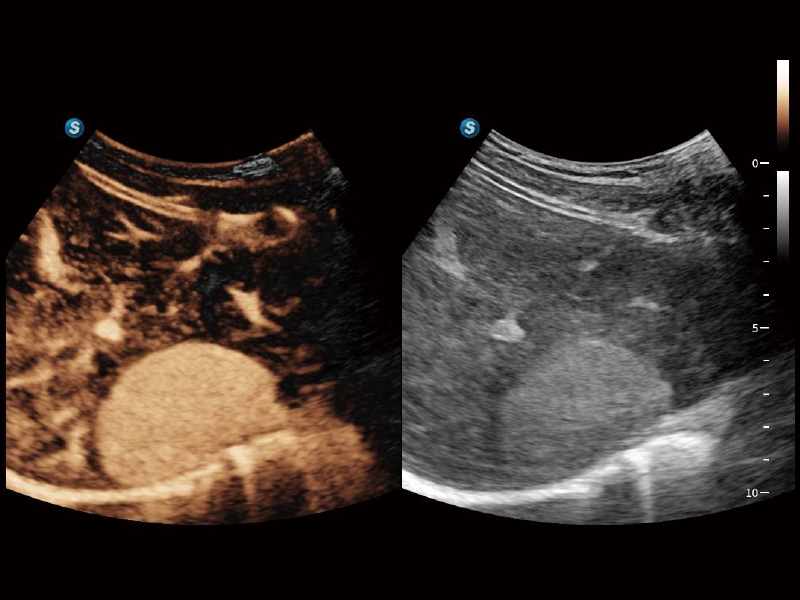

通过创新的Matrix E自适应滤波算法,能有效滤除软组织和噪声信号,最大限度保留超低速微细血流的信号;结合超长时间域算法,极大提升细微血流的敏感性和空间分辨率,更真实的反应组织、包块的血流灌注情况。